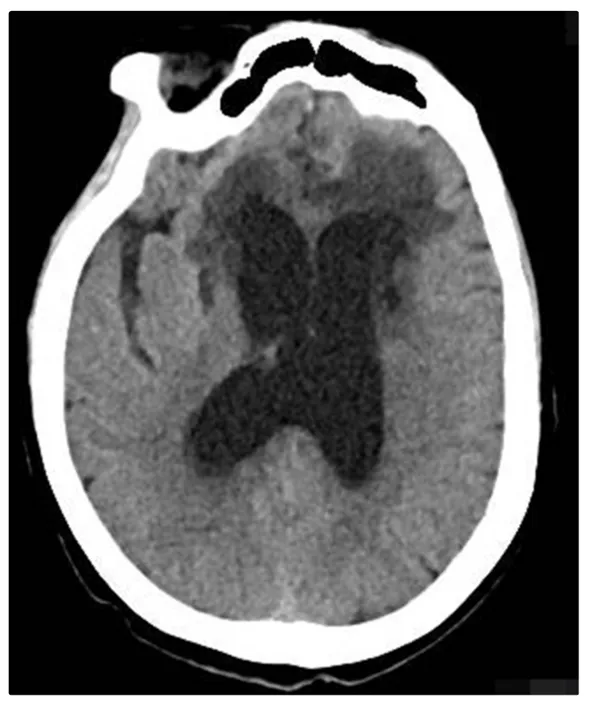

到医院一查,检查显示她的大脑额叶、颞叶多发急性脑梗死,负责记忆和认知的区域已经出现缺血坏死,同时还有颈内动脉重度狭窄。

指南推荐,怀疑脑梗,首选CT和头颅核磁共振MRI,CT能快速排查是否脑出血,MRI能清晰发现早期、微小梗死灶,尤其是负责记忆的颞叶、海马区梗死。